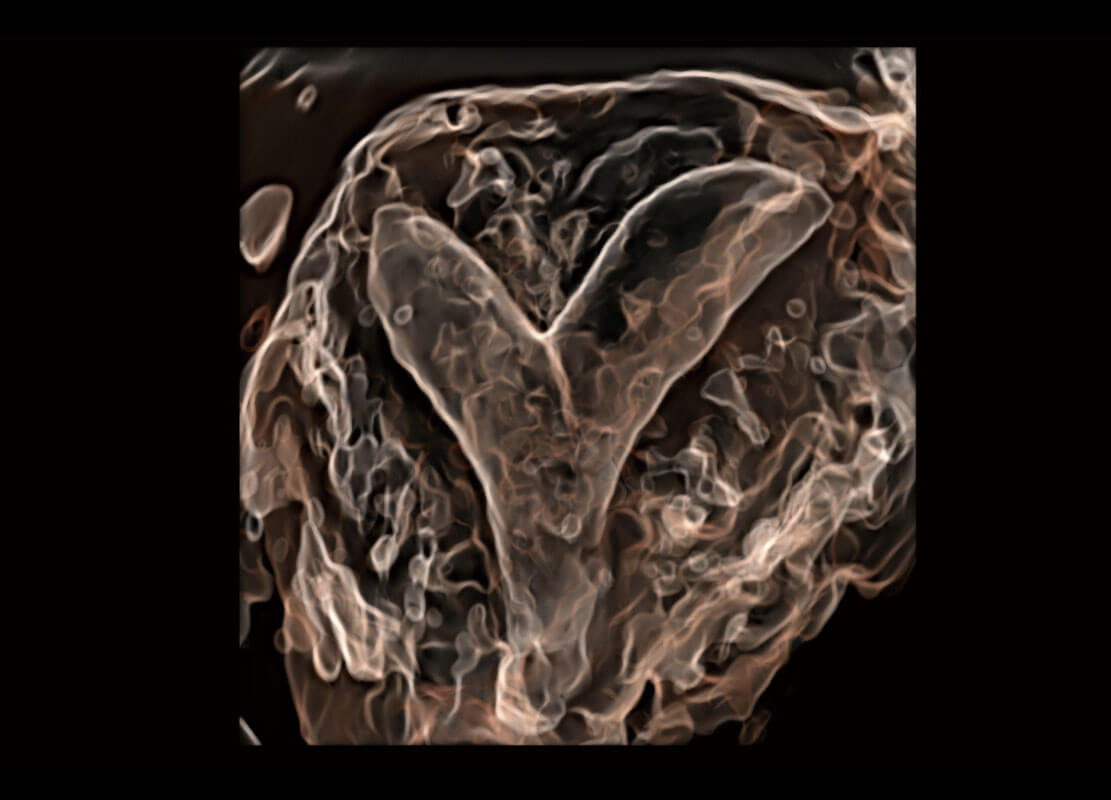

腔内三维-光影成像

高分辨率容积成像-早孕胎儿